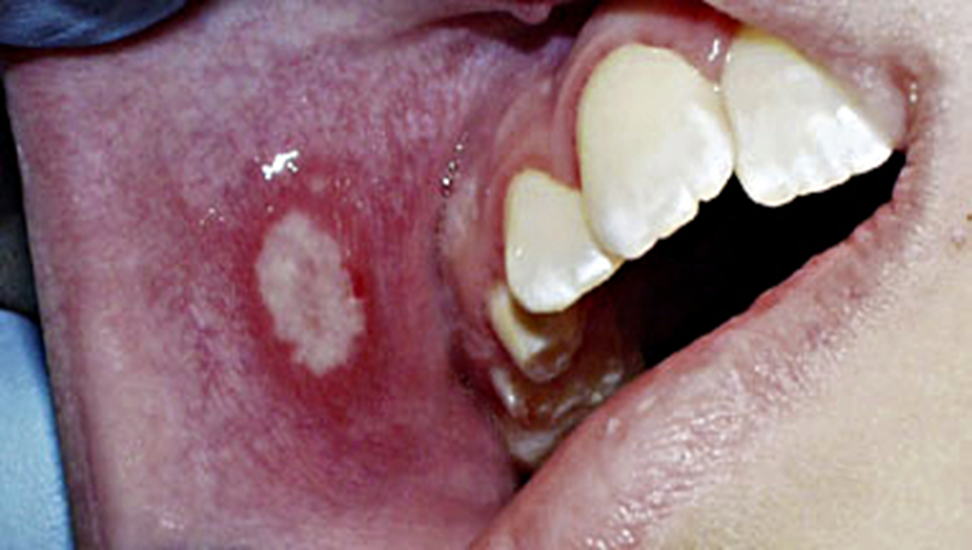

დაავადების კარდინალური ნიშანია ორალური ენანთემა (სურათი 1 ა-ბ) და ეგზანთემა (სურათი 2) , თუმცა შესაძლოა იყოს ენანთემა ეგზანთემის გარეშე, ან ეგზანთემა ენანთემის გარეშე.

სურათი 1-ბ

ორალური ენანთემა – ორალური დაზიანება შეიძლება მოიცავდეს მთელ პირის ღრუს, თუმცა უმეტესად ზიანდება სასის რკალები, ენა და ლოყის ლორწოვანი (სურათი 1 ა-ბ). შედარებით ნაკლებად ერთვება პროცესში გინგივოლაბიალური ღარი, მაგარი და რბილი სასა. ზოგჯერ მოიცავს ნაქს, ტუჩებსა და ტონზილებს.

ენანთემა იწყება ერითემატოზული მაკულებით, რომელიც პროგრესირდება ვეზიკულებად, ირგვლივ ერითემული უბნებით (სურათი 1-ბ). ვეზიკულების დიამეტრი ცვალებადობს 1მმ-დან 5 მმ-მდე. შეიძლება იყოს უფრო დიდი ზომის. ვეზიკულები სწრაფად სკდებიან და წარმოქმნიან მონაცრისფრო – მოყვითალო ზედაპირულ წყლულებს, ერითემატოზული რგოლით (სურათი 1-ა). წყლულების დიამეტრი ჩვეულებრივ 1მმ-დან 10 მმ-მდე მერყეობს, იშვიათად აღწერილია 20 მმ ზომის წყლულოვანი ელემენტებიც.

ხფპდ დიაგნოზი ჩვეულებრივ ისმება კლინიკურად ორალური ენანთემის ტიპიური ლოკალიზაციის და მიმდინარეობის (სურათი 1 ა-ბ) და ეგზანთემის (სურათი 2) მიხედვით. დიაგნოსტირება შესაძლოა გართულდეს, თუ დაავადება მხოლოდ ენანთემით ან ეგზანთემით მიმდინარეობს. თუმცა უმრავლეს შემთხვევაში დაავადება მიმდინარეობს ორივე სახის გამონაყრით და მხოლოდ 10-15 % ში გვხვდება მხოლოდ ენანთემა ან ეგზანთემა.